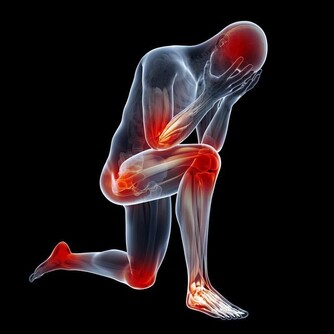

值得注意的是,膝蓋痛有可能是缺鈣、涼風寒濕痺證、骨質增生、受涼受風受濕、肝腎虛弱等所引起的。隨著年齡的增長,站立或者走路久了,膝關節都可能會發生退性行病變。初期,起病緩慢者膝關節疼痛不嚴重,可持續性隱痛,氣溫降低時疼痛加重,與氣候變化有關。

晨起後開始活動,長時間行走,劇烈運動或久坐起立開始走時膝關節疼痛僵硬,稍活動後好轉,上、下樓困難,下樓時膝關節發軟,易摔倒。蹲起時疼痛,僵硬,嚴重時,關節酸痛脹痛,跛行,關節功能受限,以下蹲最為明顯,伸屈活動有彈響聲,部分患者可見關節積液,局部有明顯腫脹、壓痛現象,合併風濕病者關節紅腫、畸形。